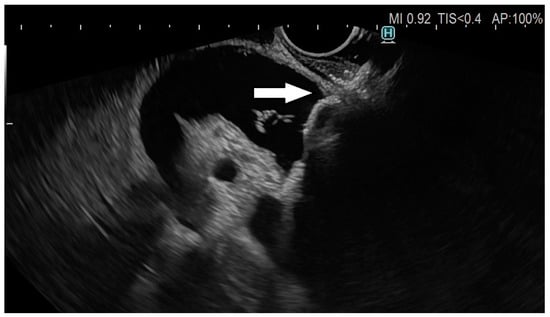

The technique of EUS-guided biliary drainage (EUS-BD) has evolved significantly over the past decade, particularly since the first clinical case of LAMS was described in 2014 [7]. In short, after the window of bile duct approach from the duodenal bulb or, less frequently, the distal stomach is identified under EUS guidance, and the cautery-enhanced device is slowly advanced into the bile duct above the level of the tumoral obstruction using pure-cut current. After penetration and proper advancement into the bile duct, the distal flange is deployed under endosonographic real-time guidance, followed by device retraction for achieving apposition of the bile duct and gastrointestinal tract, when the proximal flange of the LAMS can be safely deployed (Figure 1, Figure 2 and Figure 3). This revolutionary type of device has brought a paradigm shift in the field of interventional endoscopy, but many debates about the technical aspects of this procedure are still unresolved. We will strive to provide a pragmatic overview of the main points of contention among endoscopists performing this technique.

Figure 2. EC-LAMS inside the CBD, partial deployment of distal flange of the stent.